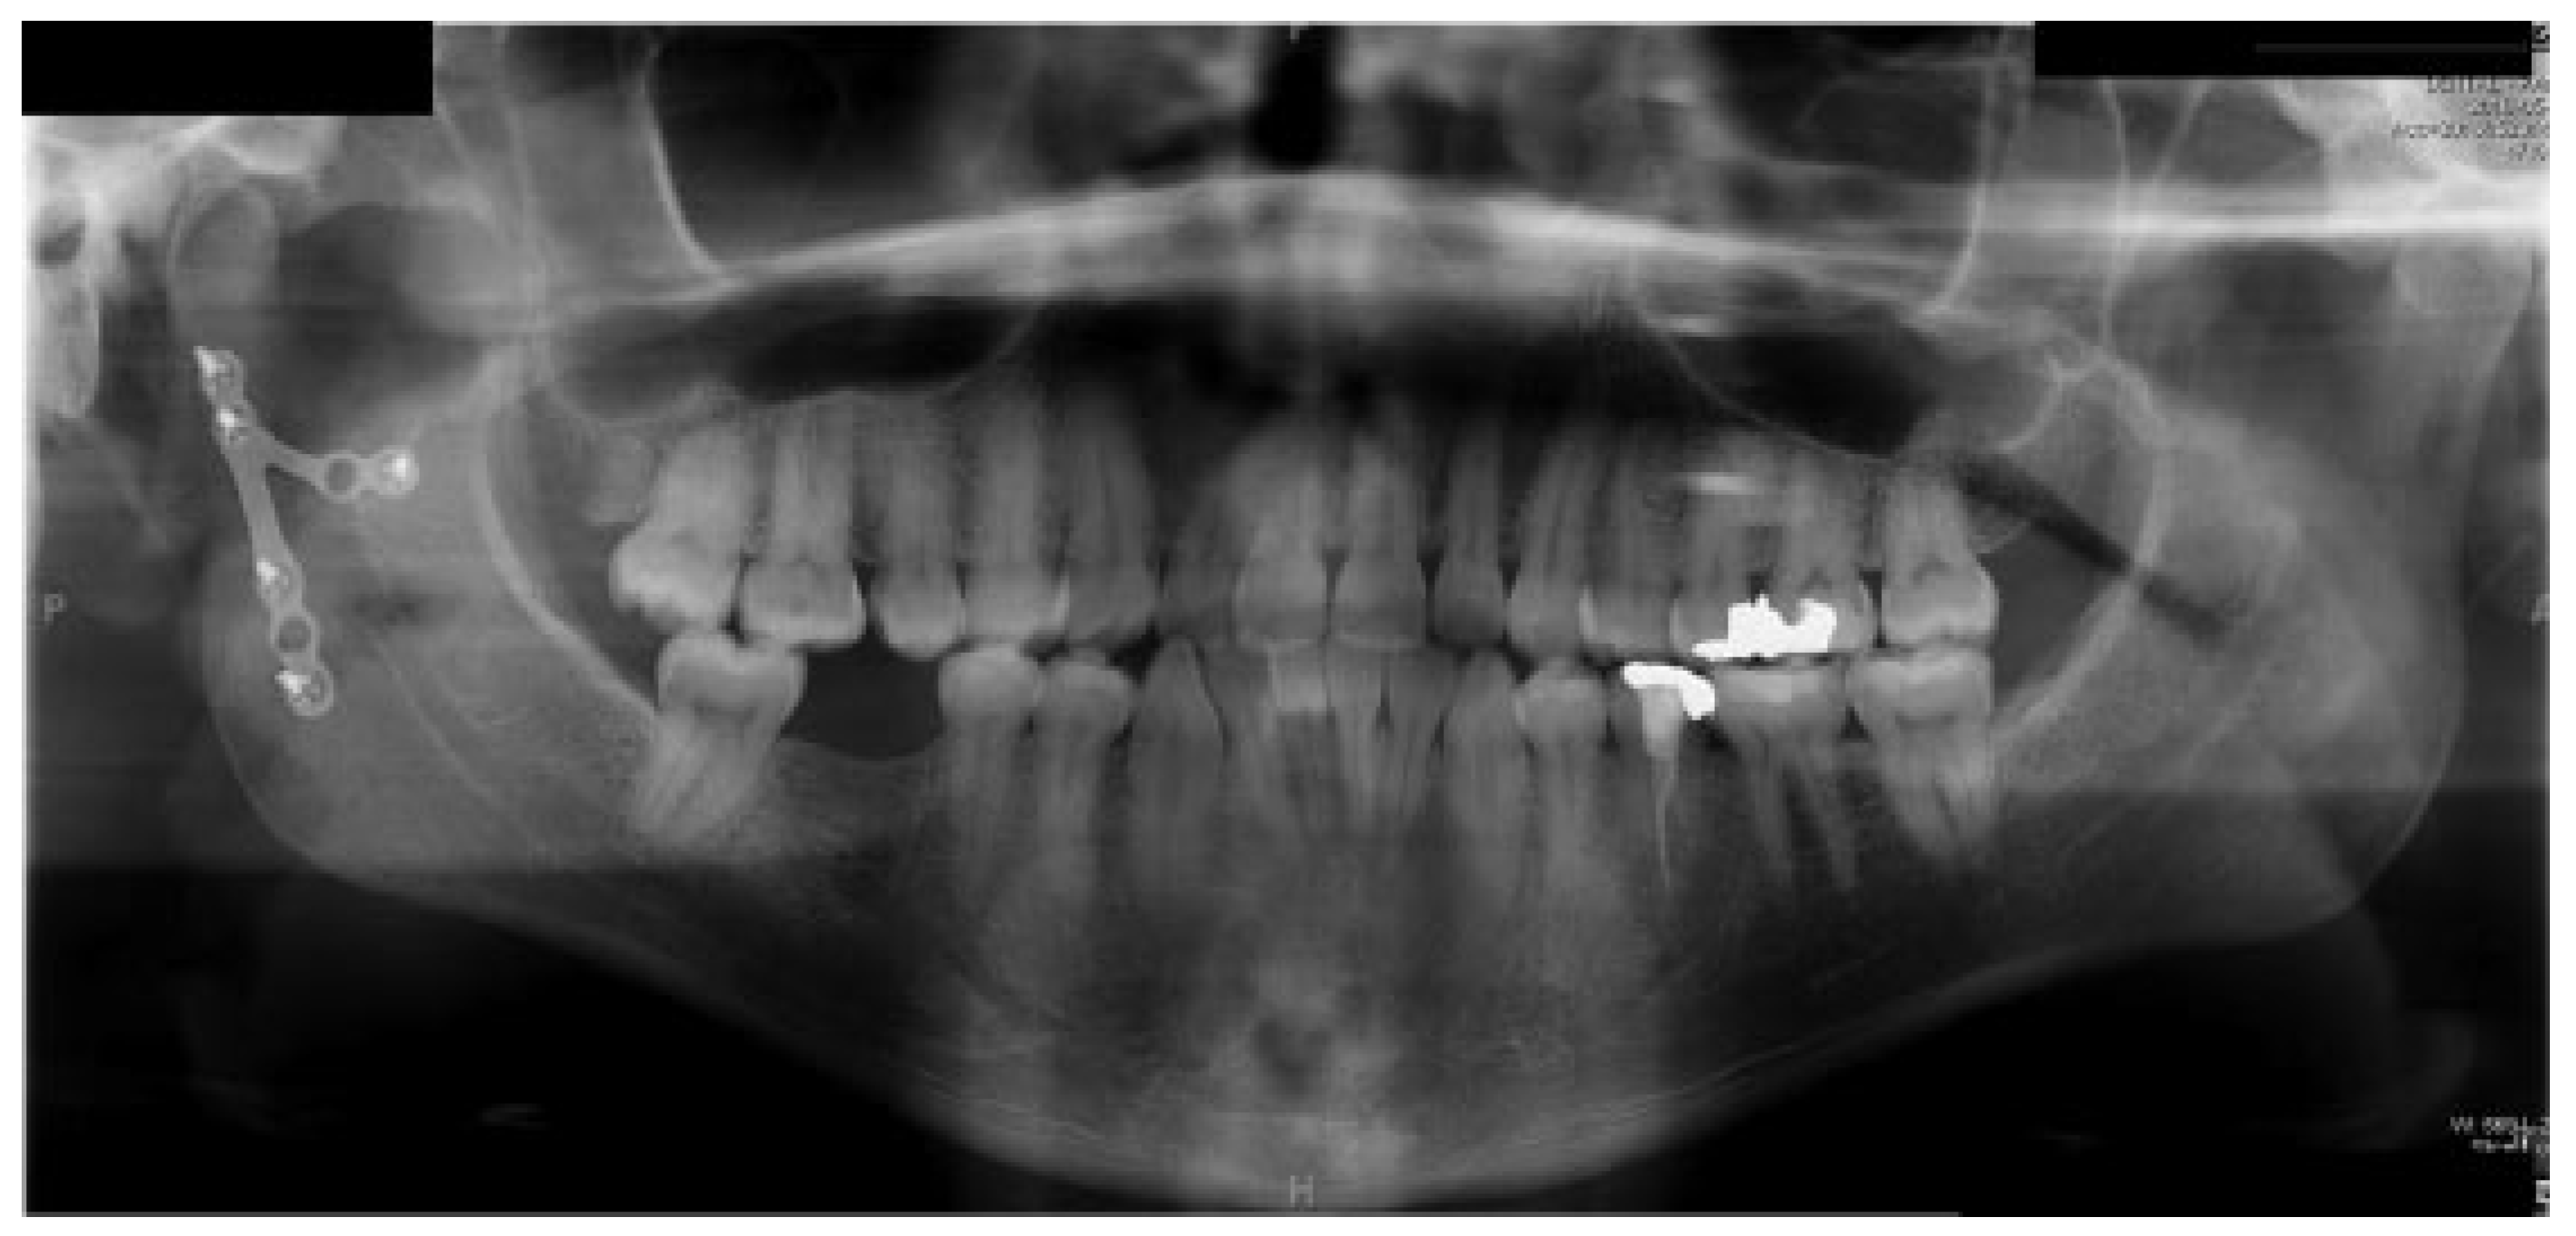

Pseudoaneurysm following Endoscopic-Assisted Repair of Subcondylar Fracture

:Presentation of Case